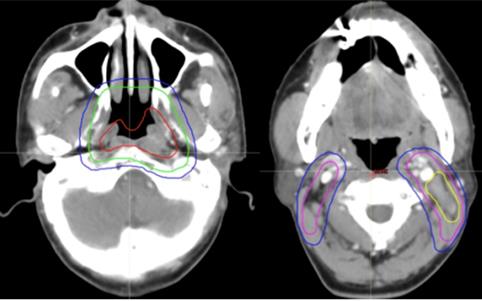

Figure 3

Selected computed tomography slices to demonstrate the delineation of different risk target volumes. Red: PGTVnx; yellow: PGTVnd; green: PTVnx; pink: PTVna; blue: PTV1. Abbreviations: PGTVnx: planning target volume of nasopharyngeal GTV; PGTVnd: planning target volume of GTV in cervical lymph nodes; PTVnx: planning target volume of nasopharynx; PTVna: planning target volune of neck area; PTV: planning target volume 1.

Figure 2

Figure 4

Selected computed tomography slices to demonstrate the delineation of low-risk target volumes. Red: PGTVnx; yellow: PGTVnd; green: PTVnx; pink: PTVna; blue: PTV1. Abbreviations: PGTVnx: planning target volume of nasopharyngeal GTV; PGTVnd: planning target volume of GTV in cervical lymph nodes; PTVnx: planning target volume of nasopharynx; PTVna: planning target volume of neck area; PTV: planning target volume 1.